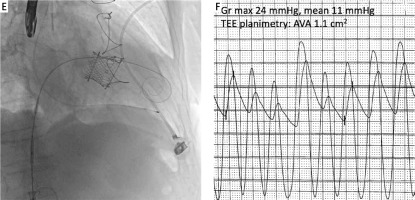

Severe mitral bio-prothesis regurgitation treated with transseptal mitral valve-in-valve implantation and subsequent assessment of borderline aortic stenosis is presented. A – Transesophageal echocardiography shows significant regurgitation of mitral biological prothesis (Hancock II 29 mm). B – After transseptal puncture, two small Safari wires were inserted into the left ventricle with the help of an Agilis catheter (Abbott) and 7F JR4 catheter, then an Edwards eSheath introducer was placed over one of the wires (i.e. a working wire) – another wire served as a buddy wire and was kept outside the eSheath. C – Using the working Safari wire, a balloon septostomy was performed with a 14 mm Valver balloon (Balton). D – The SAPIEN3 valve was delivered, then the buddy wire was removed and the valve was implanted during prolonged fast cardiac pacing E – To ensure a conical shape of the implanted valve and prevent its late migration to the left atrium an oversized 29 mm SAPIEN3 valve was used in this case. F – Immediately after the procedure, the aortic valve gradient and aortic valve area measurements revealed features of moderate stenosis

Gr – gradient, TEE – transesophageal echocardiography, AVA – aortic valve area.

After successful implantation, the invasive and non-invasive evaluation revealed a moderate degree of AVS (AVA 1.1 cm2, maximal/mean gradient 24/11 mm Hg), and hence, TAVI was abandoned. During 6-month follow-up, the patient was asymptomatic with good function of the implanted SAPIEN3 valve and no signs of progression of aortic stenosis. This case shows that a transcatheter approach may help to manage multivalvular heart disease in an evidence-based manner.